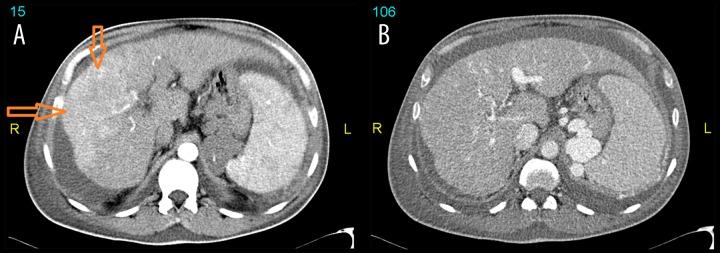

A 66-year-old male with a background of type 2 diabetes mellitus and post-alcoholic decompensated liver cirrhosis presented with a progressively enlarging painful right facial swelling for 2 months that was eventually found to be due to hepatocellular carcinoma metastatic to the right parotid gland. Fine needle aspiration from the right parotid showed sheets and single malignant cells that were interpreted as carcinoma not otherwise specific. However, biopsy showed metastatic hepatocellular carcinoma into the right parotid gland.

一名66岁男性,有2型糖尿病和酒精性失代偿期肝硬化病史,右侧面部逐渐增大的疼痛性肿胀2个月,最终发现是由于肝细胞癌转移至右侧腮腺。右侧腮腺细针穿刺显示成片及单个恶性细胞,诊断为非特异性癌。然而,活检显示为转移性肝细胞癌累及右侧腮腺。